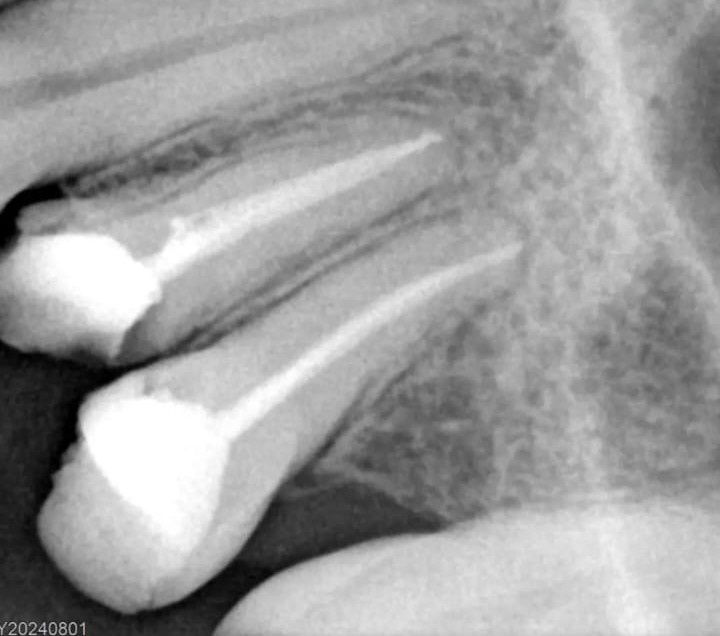

Veja alguns casos de sucesso